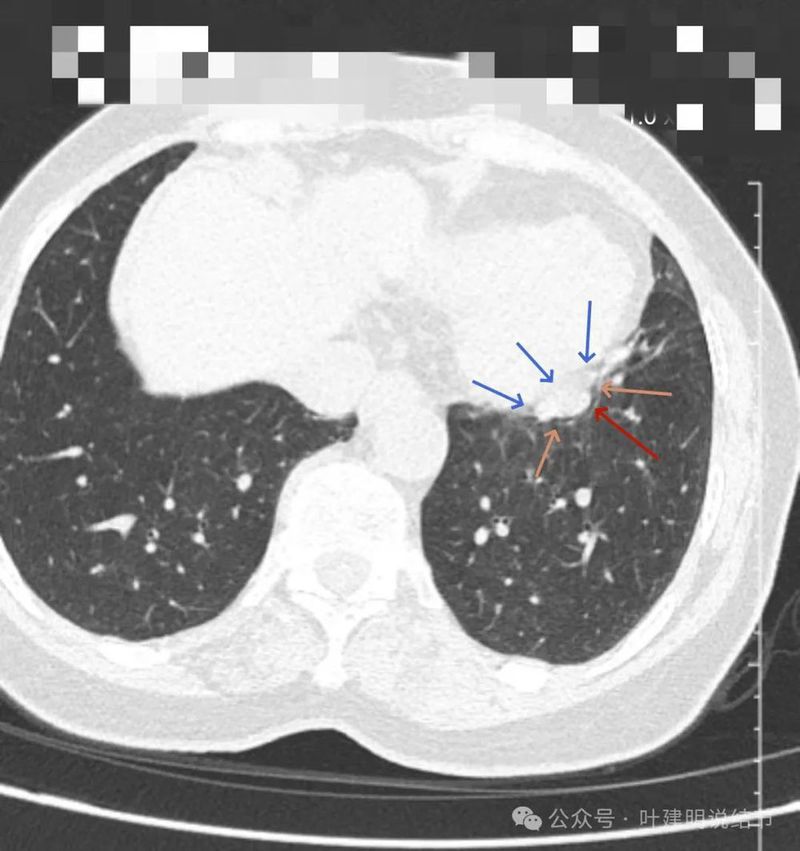

病灶浅分叶,膨胀性,周围有很淡的磨玻璃密度似的,这可能是检查时屏气屏得不太好的关系,不太符合混合磨玻璃结节的样子。

整体感觉较圆,膨胀性是明显的。膈肌有点被它顶过去的样子。

上图层面相对最大,感觉鼓鼓的。

纵隔窗见病灶实性密度,与膈肌间有低密度线状间隙。

病灶密度稍不均。